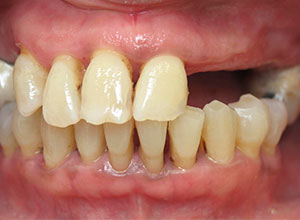

Se utiliza en pacientes completamente edéntulos, es decir, que no tienen ninguna pieza dental, ya sea en el maxilar, en la mandíbula o, incluso, en ambos. Y, que, además, presentan una pérdida moderada de hueso.

Por otro lado, este tipo de rehabilitación también está indicada en aquellas personas que, aunque aún mantienen dientes en la boca, dichas piezas dentales presentan un pronóstico imposible a corto plazo y están abocados al edentulismo total.